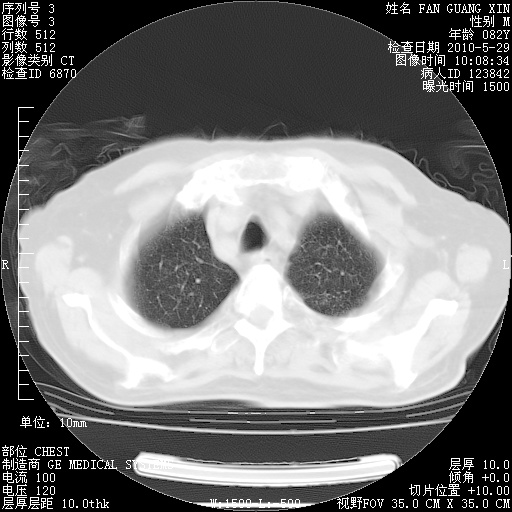

再治疗10天后的肺部CT